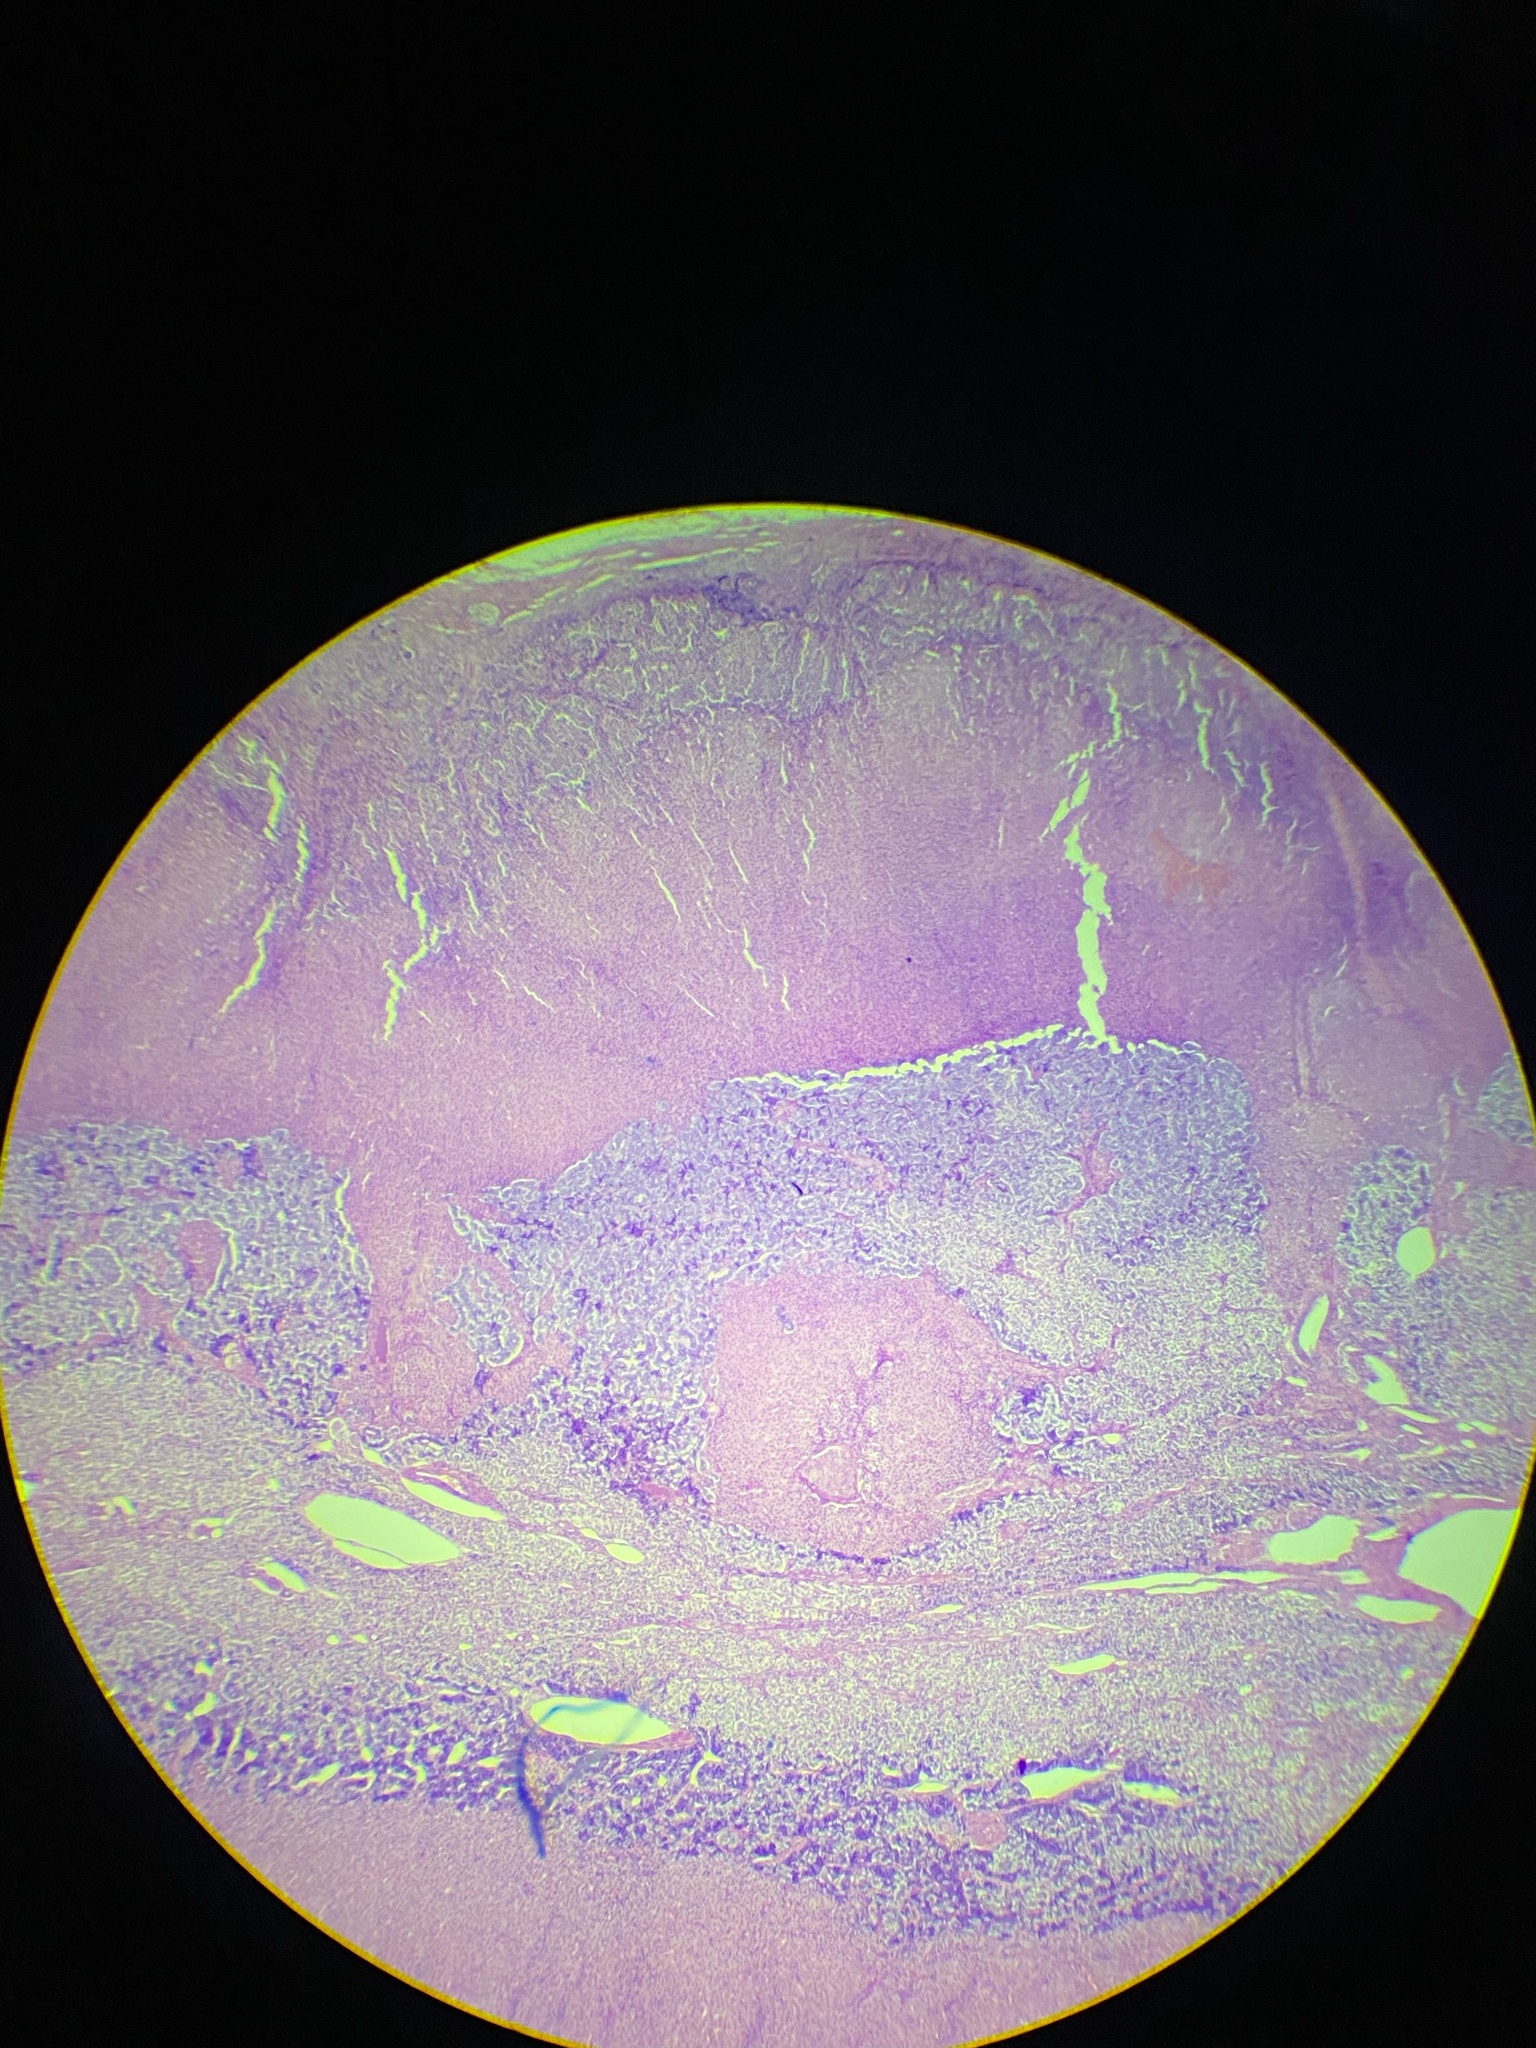

Digital Microscopy Image 4

Adrenal gland, human. Light microscope 4x objective